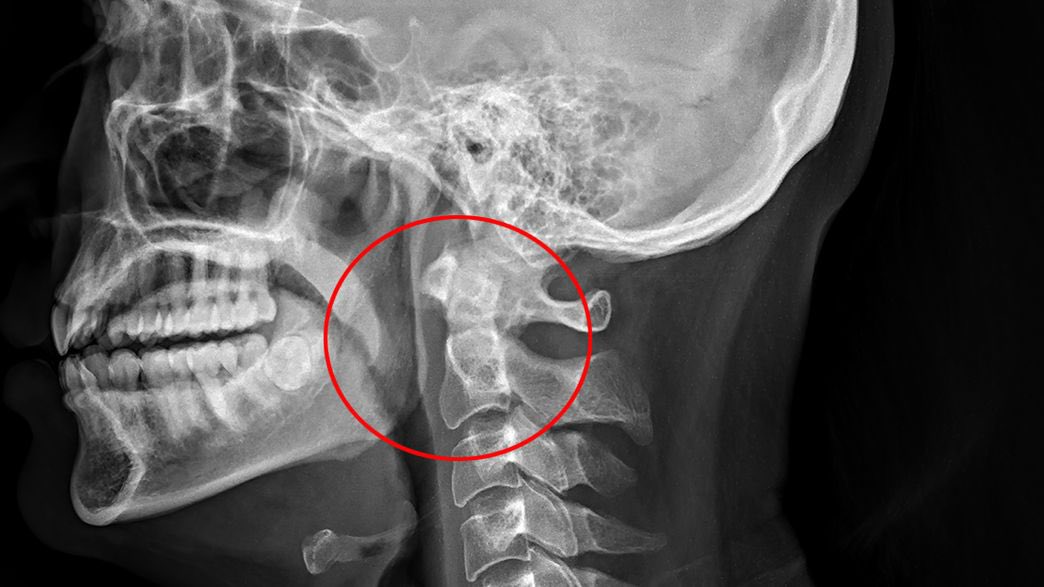

حيث أظهر التصوير الشعاعي الجانبي للرقبة الأنسجة الرخوة خطوطًا من الهواء في منطقة خلف البلعوم وانتفاخ رئوي جراحي واسع النطاق في الرقبة الأمامية للقصبة الهوائية

بجانب التصوير المقطعي المحوسب العاجل للرقبة والصدر مع التباين أكدّ وجود انتفاخ رئوي واسع النطاق للأنسجة الرخوة يتركز في الغالب داخل الرقبة بالإضافة إلى استرواح المنصف الممتد من قاعدة الجمجمة وصولاً إلى الفقرة T9